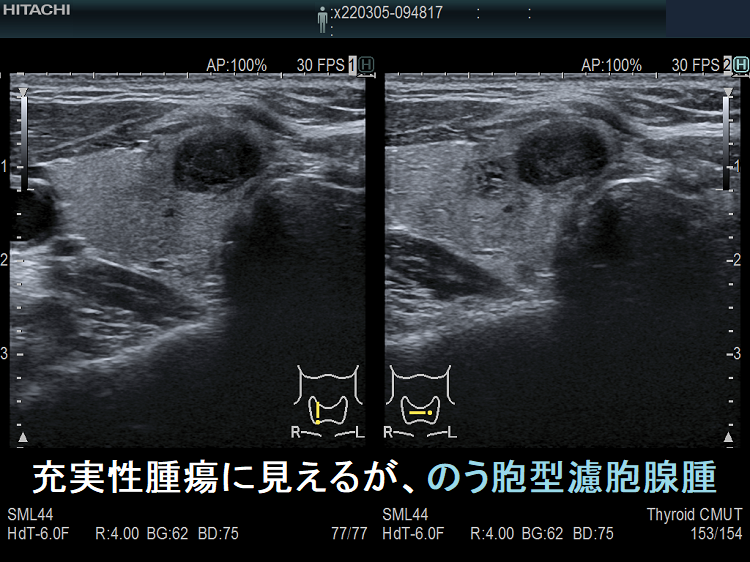

たとえば、通常Bモードでは、

1. のう胞(嚢胞)に見えても、高感度パワードプラーで低流速の細い血管が検出され、実は真っ黒な(極めて低エコーな)甲状腺腫瘍 [甲状腺のう胞(甲状腺嚢胞)に見えるが甲状腺腫瘍]

2. 充実性腫瘍に見えても、高感度パワードプラーで低流速の細い血管が検出されず、実はただの甲状腺のう胞腺腫(甲状腺嚢胞腺腫)(内部の不均質な実質様エコーは粘稠なコロイド物質)

だったなど、臨床診断が覆る場合があります。特に1.の場合は、甲状腺腫瘍甲状腺のう胞(甲状腺嚢胞)と間違えると大変な事になります。極めて低エコーな甲状腺腫瘍は、甲状腺乳頭癌甲状腺濾胞癌甲状腺髄様癌甲状腺悪性リンパ腫の可能性があるからです。

ケース⑤ 甲状腺充実性腫瘍でなく甲状腺のう胞腺腫(甲状腺嚢胞腺腫)

充実性腫瘍に見えるが、のう胞腺腫

通常Bモードでは、充実性腫瘍に見える。

高感度パワードプラーで低流速の細い血管が検出されず、甲状腺のう胞腺腫(甲状腺嚢胞腺腫)(内部の不均質な実質様エコーは粘稠なコロイド物質)